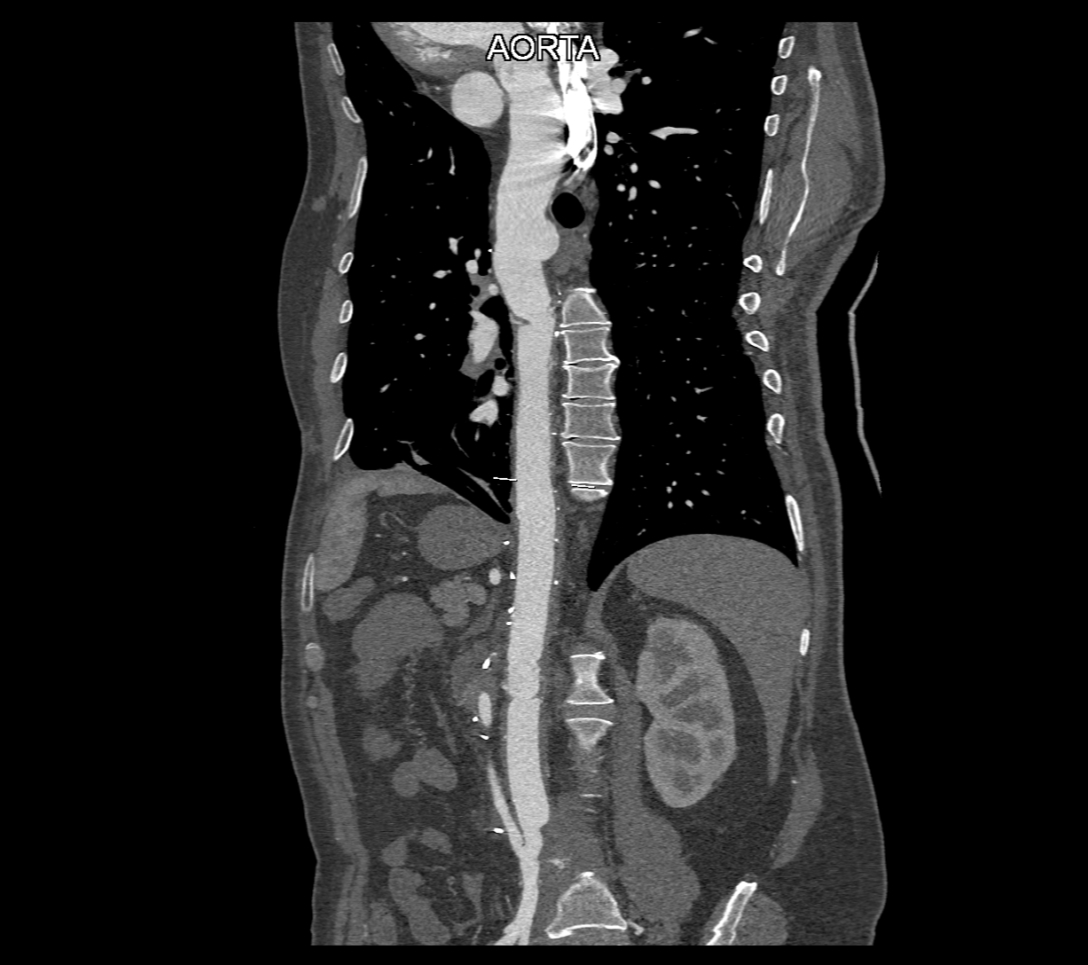

Figurile 2, 3 și 4: reconstrucţii oblic coronale aortă postoperator